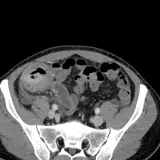

Body CT